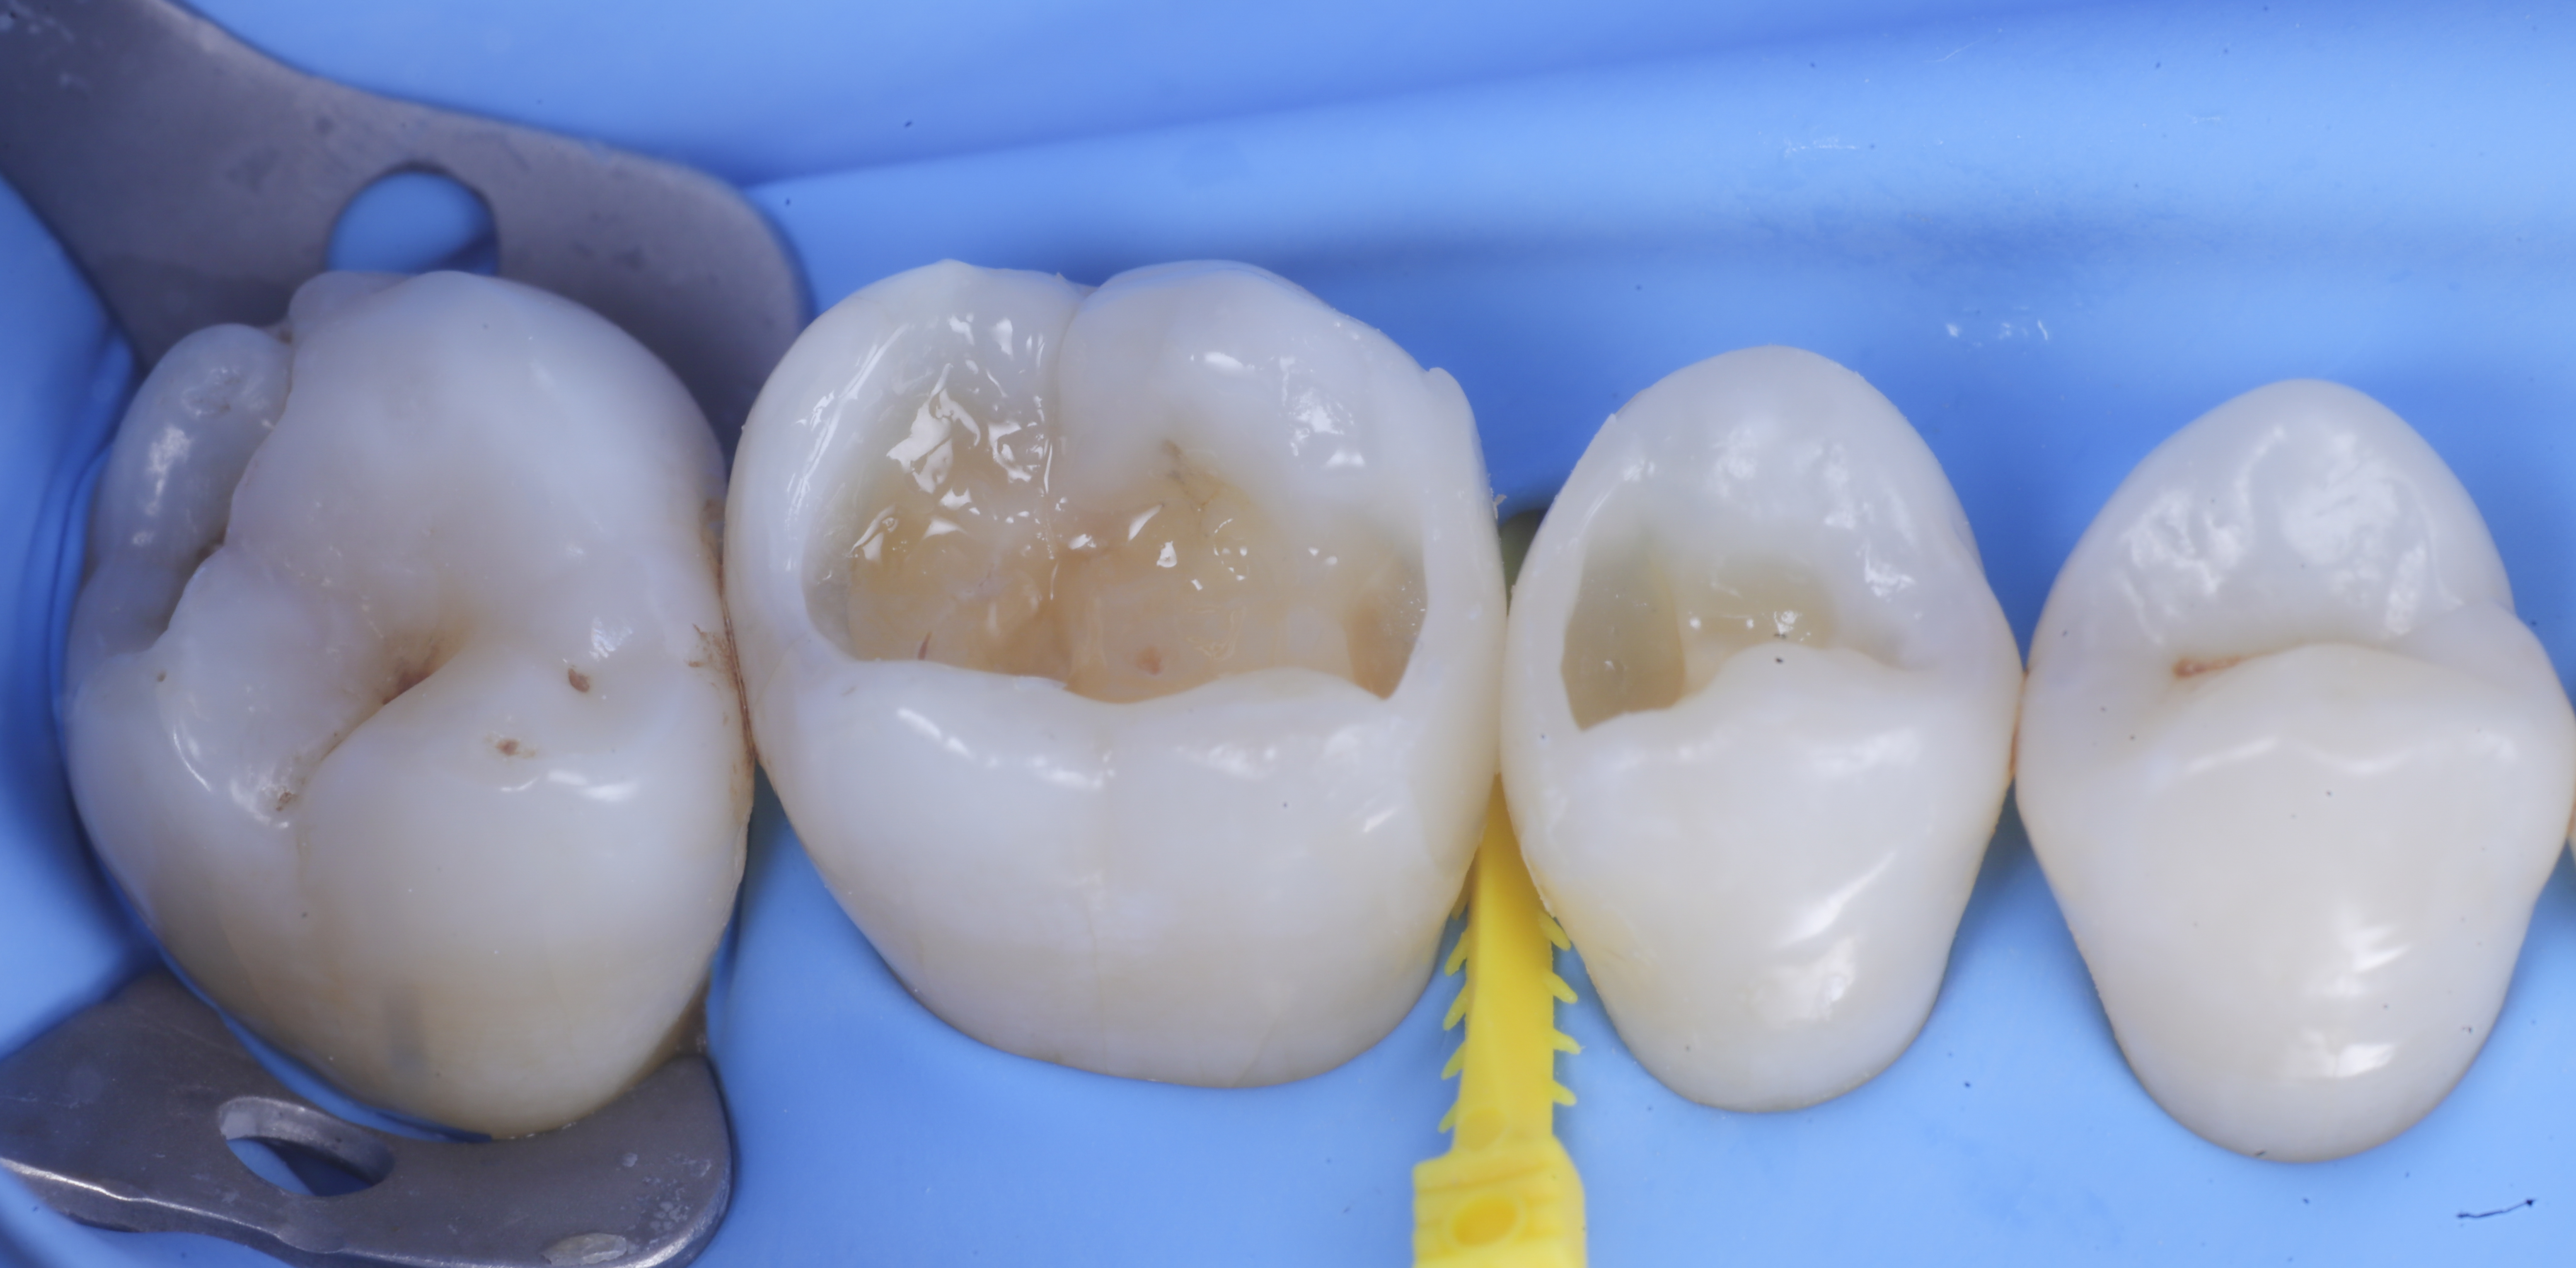

foto 2 Isolamento e aspetto delle cavità ultimate

foto 3 Aspetto vestibolare della cavità ultimate